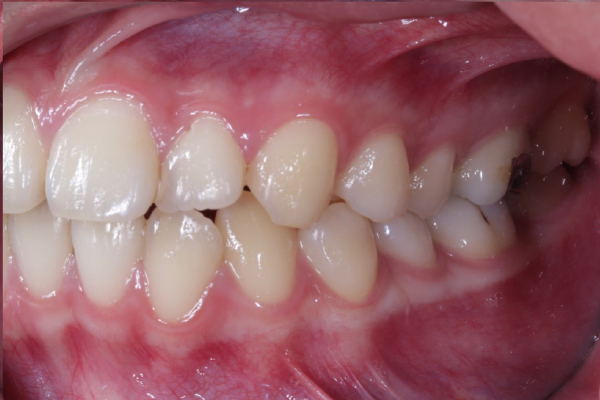

AFTER

本症例では適切なタイミングで診断と介入を行えたことで、矯正的牽引により永久犬歯を歯列内へ誘導することができました。

犬歯は咬合誘導および審美性に重要な役割を担う歯であり、早期の診断が将来的な咬合安定につながります。

今後は保定管理および定期的な経過観察を行っていきます。